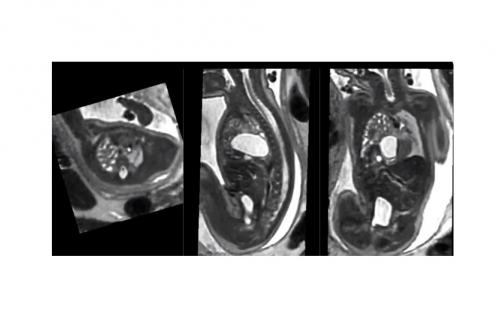

核磁共振成像(MRI)可更精确地检测、定义及表征未出生胎儿的异常和缺陷

23/03/2021